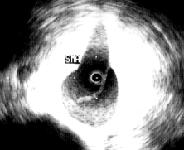

(三)超声心动图 对诊断升主动脉夹层分离具有重要意义,且易识别并发症(如心包积血、主动脉瓣关闭不全和胸腔积血等)。在M型超声中可见主动脉根部扩大,夹层分离处主动脉壁由正常的单条回声带变成两条分离的回声带。在二维超声中可见主动内分离的内膜片呈内膜摆动征,主动脉夹层分离形成主动脉真假双腔征。有时可见心包或胸腔积液。多普勒超声不仅能检出主动脉夹层分离管壁双重回声之间的异常血流,而且对主动脉夹层的分型、破口定位及主动脉瓣返流的定量分析都具有重要的诊断价值。应用食管超声心动图。结合实时彩色血流显像技术观察升主动脉夹层分离病变较可靠。对降主动脉夹层也有较高的特异性及敏感性。